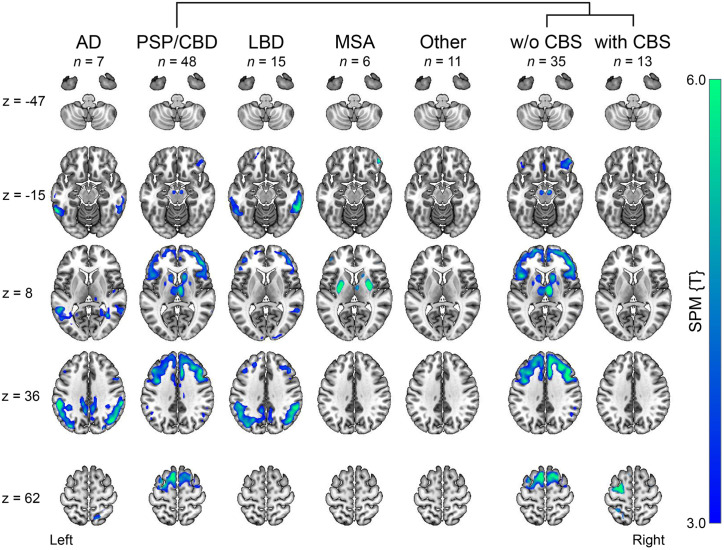

Patient flow is shown Supplemental Figure 1. Patient characteristics are summarized in Table 1. Clinical consensus diagnoses were as follows: 51 PSP/CBD (16 PSP-RS, 13 PSP with predominant parkinsonism, 6 PSP/CBS, 4 PSP with predominant frontal presentation, 5 PSP without clear predominance type, and 7 CBD-CBS), 15 LBD (7 PD, 4 PDD, and 4 DLB), 6 MSA (all MSA with predominant parkinsonism), 8 AD (among them, 2 AD-CBS), 3 FTD (1 behavioral variant FTD and 2 nonfluent variant primary progressive aphasia), and 11 other (7 nonneurodegenerative disease, 2 subcortical leukoencephalopathy, 1 amyotrophic lateral sclerosis, and 1 Creutzfeldt–Jakob disease). Figure 1 and Supplemental Figure 2 depict the typical disease-specific patterns of cerebral glucose metabolism in the different disease groups (including stratification by dementia of LBD and individual FTD cases, given their low number), supporting the validity of the interdisciplinary consensus diagnosis. There were no differences between groups for age at PET (F5,88 = 1.5, P = 0.21) and symptom duration (F5,85 = 1.4, P = 0.24; albeit longer in LBD). Average Mini-Mental State Examination scores indicated mild dementia in LBD, AD, and FTD patients without significant differences compared with other groups (F5,68 = 1.6, P = 0.17). Overall motor impairment, as assessed by the Hoehn and Yahr scale, was on a trend level higher in MSA (strongly impaired) than in patients with PSP/CBD (moderate impairment; F3,63 = 3.3, P = 0.03; Tukey honest significant difference test, MSA vs. PSP/CBD, P = 0.08). The rank order was similar on a more detailed assessment with Unified Parkinson Disease Rating Scale part III without significant group differences (F4,49 = 0.25, P = 0.91).

Figure 2 depicts representative transaxial slices of average [18F]florzolotau PET images of each group. Figure 3 and Supplemental Table 1 illustrate the proportion of visual ratings for 4R-like or AD-like patterns in the different patient groups. The 3 raters reached substantial agreement for the classification of 4R-like (κ range, 0.78–0.97) and AD-like (κ range, 0.88–0.96) patterns (higher agreement between more experienced raters, 0.97 vs. 0.84).

The expected 4R-like pattern from the literature was replicated by the present sample (Fig. 2). This 4R-like pattern was more highly prevalent (84.3%) and expressed (mean score, 2.0 ± 1.1) in the PSP/CBD group than in all other disease groups (pooled prevalence, 11.6%; mean score, 0.26 ± 0.75; P < 0.0001 compared with the 4R group). The pattern was observed in most PSP/CBD cases with moderate to strong expression (12/51 [23.5%] and 24/51 [47.1%], respectively), whereas only few patients with PSP/CBD showed no or mild pattern expression (8/51 [15.7%] and 7/51 [13.7%], respectively). Consensus ratings did not significantly differ between patients without CBS (2.2 ± 1.1) and with CBS (1.5 ± 1.2, P = 0.08). However, the gradient of binding was significantly different: patients with PSP/CBD without CBS (PSP, according to consensus diagnoses) showed more pronounced subcortical binding (gradient rating, 0.3 ± 0.7), whereas those with CBS exhibited more cortical binding (gradient rating, 1.6 ± 0.5; P < 0.0001).

In turn, the 4R-like pattern was not detected in any AD and LBD cases. One of 3 (33.3%) FTD cases was rated to show a strong 4R-like pattern (not present in the remaining 2 cases), whereas only 1 of 6 (16.7%) MSA cases showed moderate 4R-like pattern expression (not present in the remaining 5 cases). Three of 11 patients with other diagnoses were rated as showing a mild, moderate, and strong 4R-like pattern (final diagnoses of nonneurodegenerative disease, subcortical leukoencephalopathy, and nonneurodegenerative disease, respectively).

The AD-like pattern was also well replicated in the present sample (Fig. 2). Consensus ratings indicated strong and mild AD-like pattern expression in 6 of 8 (75.0%) and 2 of 8 (25.0%) patients, respectively (i.e., prevalence of 100% and mean score of 2.5 ± 0.9 in the AD group). The AD-like pattern was also frequently present in other patient groups (pooled prevalence, 67.4%), albeit at a lower magnitude (mean score, 1.2 ± 1.1; P < 0.01 compared with the AD group): moderate and strong AD-like pattern expression was rated in a substantial fraction of LBD cases (moderate, 4/15 [26.7%], 3/7 PD and 1/4 PDD; strong, 6/15 [40.0%], 2/4 PDD and 4/4 DLB) and a few PSP/CBD cases (moderate, 7/51 [13.7%]; strong, 5/51 [9.8%]; at higher frequency in patients with CBS [6/13] than without CBS [6/38]). The remaining LBD (5/15 [33.3%], 4 PD and 1 PDD), PSP/CBD (39/51 [76.5%]), FTD (3/3), and MSA (except 1/6 with moderate pattern expression) patients showed no or mild AD-like pattern expression (Fig. 3). In patients with other diagnoses, AD-like pattern ratings were roughly equally distributed across the 4 grades (Fig. 3).

Previously described binding patterns for clinically likely 4R tauopathies and AD were well replicated in the present cohort (ref. 1,ref. 3,ref. 8). This also applies to the binding gradient of the 4R-like pattern. Most patients correctly assigned to the PSP/CBD group had no CBS. These patients showed subcortical dominant binding in 81.8%. However, all cases with CBS (clinical consensus diagnosis of PSP-CBS and CBD-CBS with an 4R-like pattern score ≥ 1, 5 cases each) showed predominantly cortical binding (60.0%) or balanced binding between cortical and subcortical structures (40.0%). This was also the case in 6 patients with PSP/CBD without clinical CBS (balanced, 1 PSP-RS; cortical predominance, 3 PSP without a clear predominance type and 2 PSP with predominant frontal presentation). Although a comparably severe 4R tau pathology in cortical areas can be expected in PSP with predominant frontal presentation (ref. 9), this may imply that cortical 4R tau pathology precedes the clinical manifestation of cortical symptoms and CBS in the other cases. Therefore, a possibly predictive value of the binding gradient requires further research. Overall, the results confirm the approach of the current study to consider the binding of [18F]florzolotau not only as a diagnostic marker for a subset such as PSP-RS but also as a marker for the entire group of 4R tauopathies.

Previous studies with [18F]florzolotau selected patients with parkinsonism according to their established clinical diagnoses (ref. 1,ref. 3,ref. 28,ref. 29). In contrast, consecutive enrollment for this study includes patients with uncertain diagnoses, including less typical presentations, mixed pathologies, and comorbidities. Consequently, the present cohort reflects the clinical reality and the need for more advanced diagnostic options in unclear cases, what we consider a particular strength of this study. We cannot exclude that the lack of healthy controls may have affected the results. However, according to prior studies (ref. 1,ref. 3,ref. 8), we do not expect controls to show a stronger 4R-like pattern than the present non-PSP/CBD groups, so this effect should be minimal. Another strength of the present study is the masked, interdisciplinary consensus diagnosis used as a reference standard, because it incorporates comprehensive clinical data and extensive auxiliary examinations such as cognitive assessment, cerebrospinal fluid markers, and imaging (ref. 21,ref. 32). Among the biomarkers, the availability of [18F]FDG PET in almost all patients (96%) provides highly valuable information for the differentiation of neurodegenerative parkinsonian syndromes (Fig. 1) (ref. 15). Although autopsy data suggest that [18F]FDG PET can discriminate between PSP and CBD (ref. 17), further confirmatory data are needed, and the distinction between PSP and CBD by [18F]FDG PET in the present study (not relevant for the primary analysis) has to be contemplated with caution.